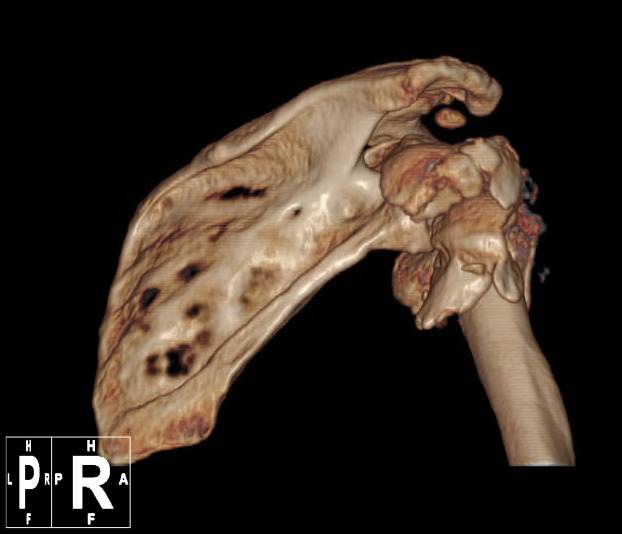

术前肱骨头CT

1、右肱骨近端骨折(Neer 4部分)